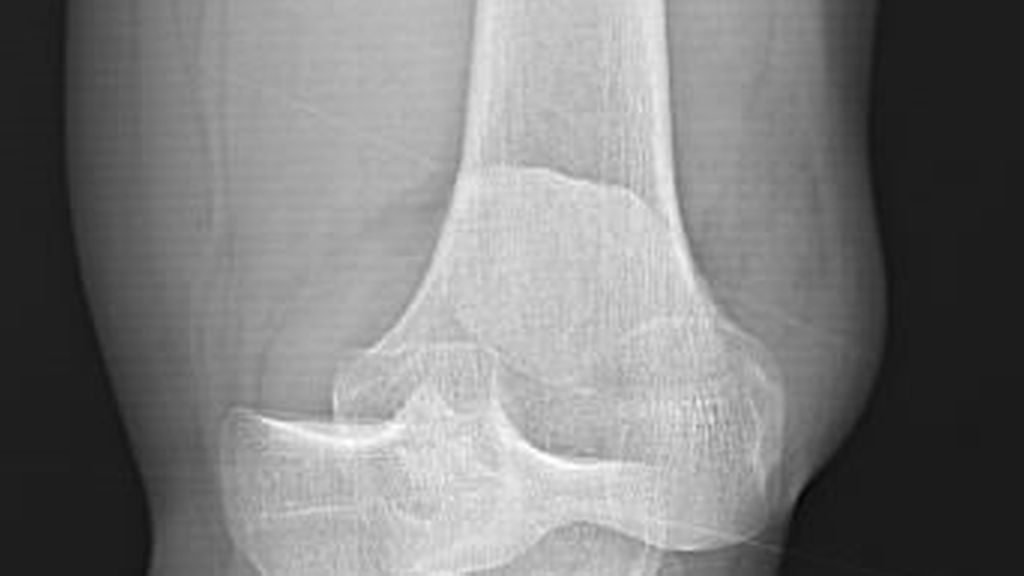

Die Patellafraktur ist eine seltene (1%), aber komplikationsbehaftete Fraktur.1 Bei fast einem Drittel der Patienten kommt es postoperativ zu belastungsabhängigen Schmerzen, chronischen ...

Luxationen des Kniegelenks sind sehr seltene, aber schwerwiegende Verletzungen, die häufig mit Komplikationen einhergehen und unbehandelt zu schweren Instabilitäten im Knie führen können ...

Revisionsoperationen am Kniegelenk stellen hohe Anforderungen an das Knochendefektmanagement. Dieser Beitrag beleuchtet aktuelle Verfahren zur metaphysären Defektrekonstruktion – von ...